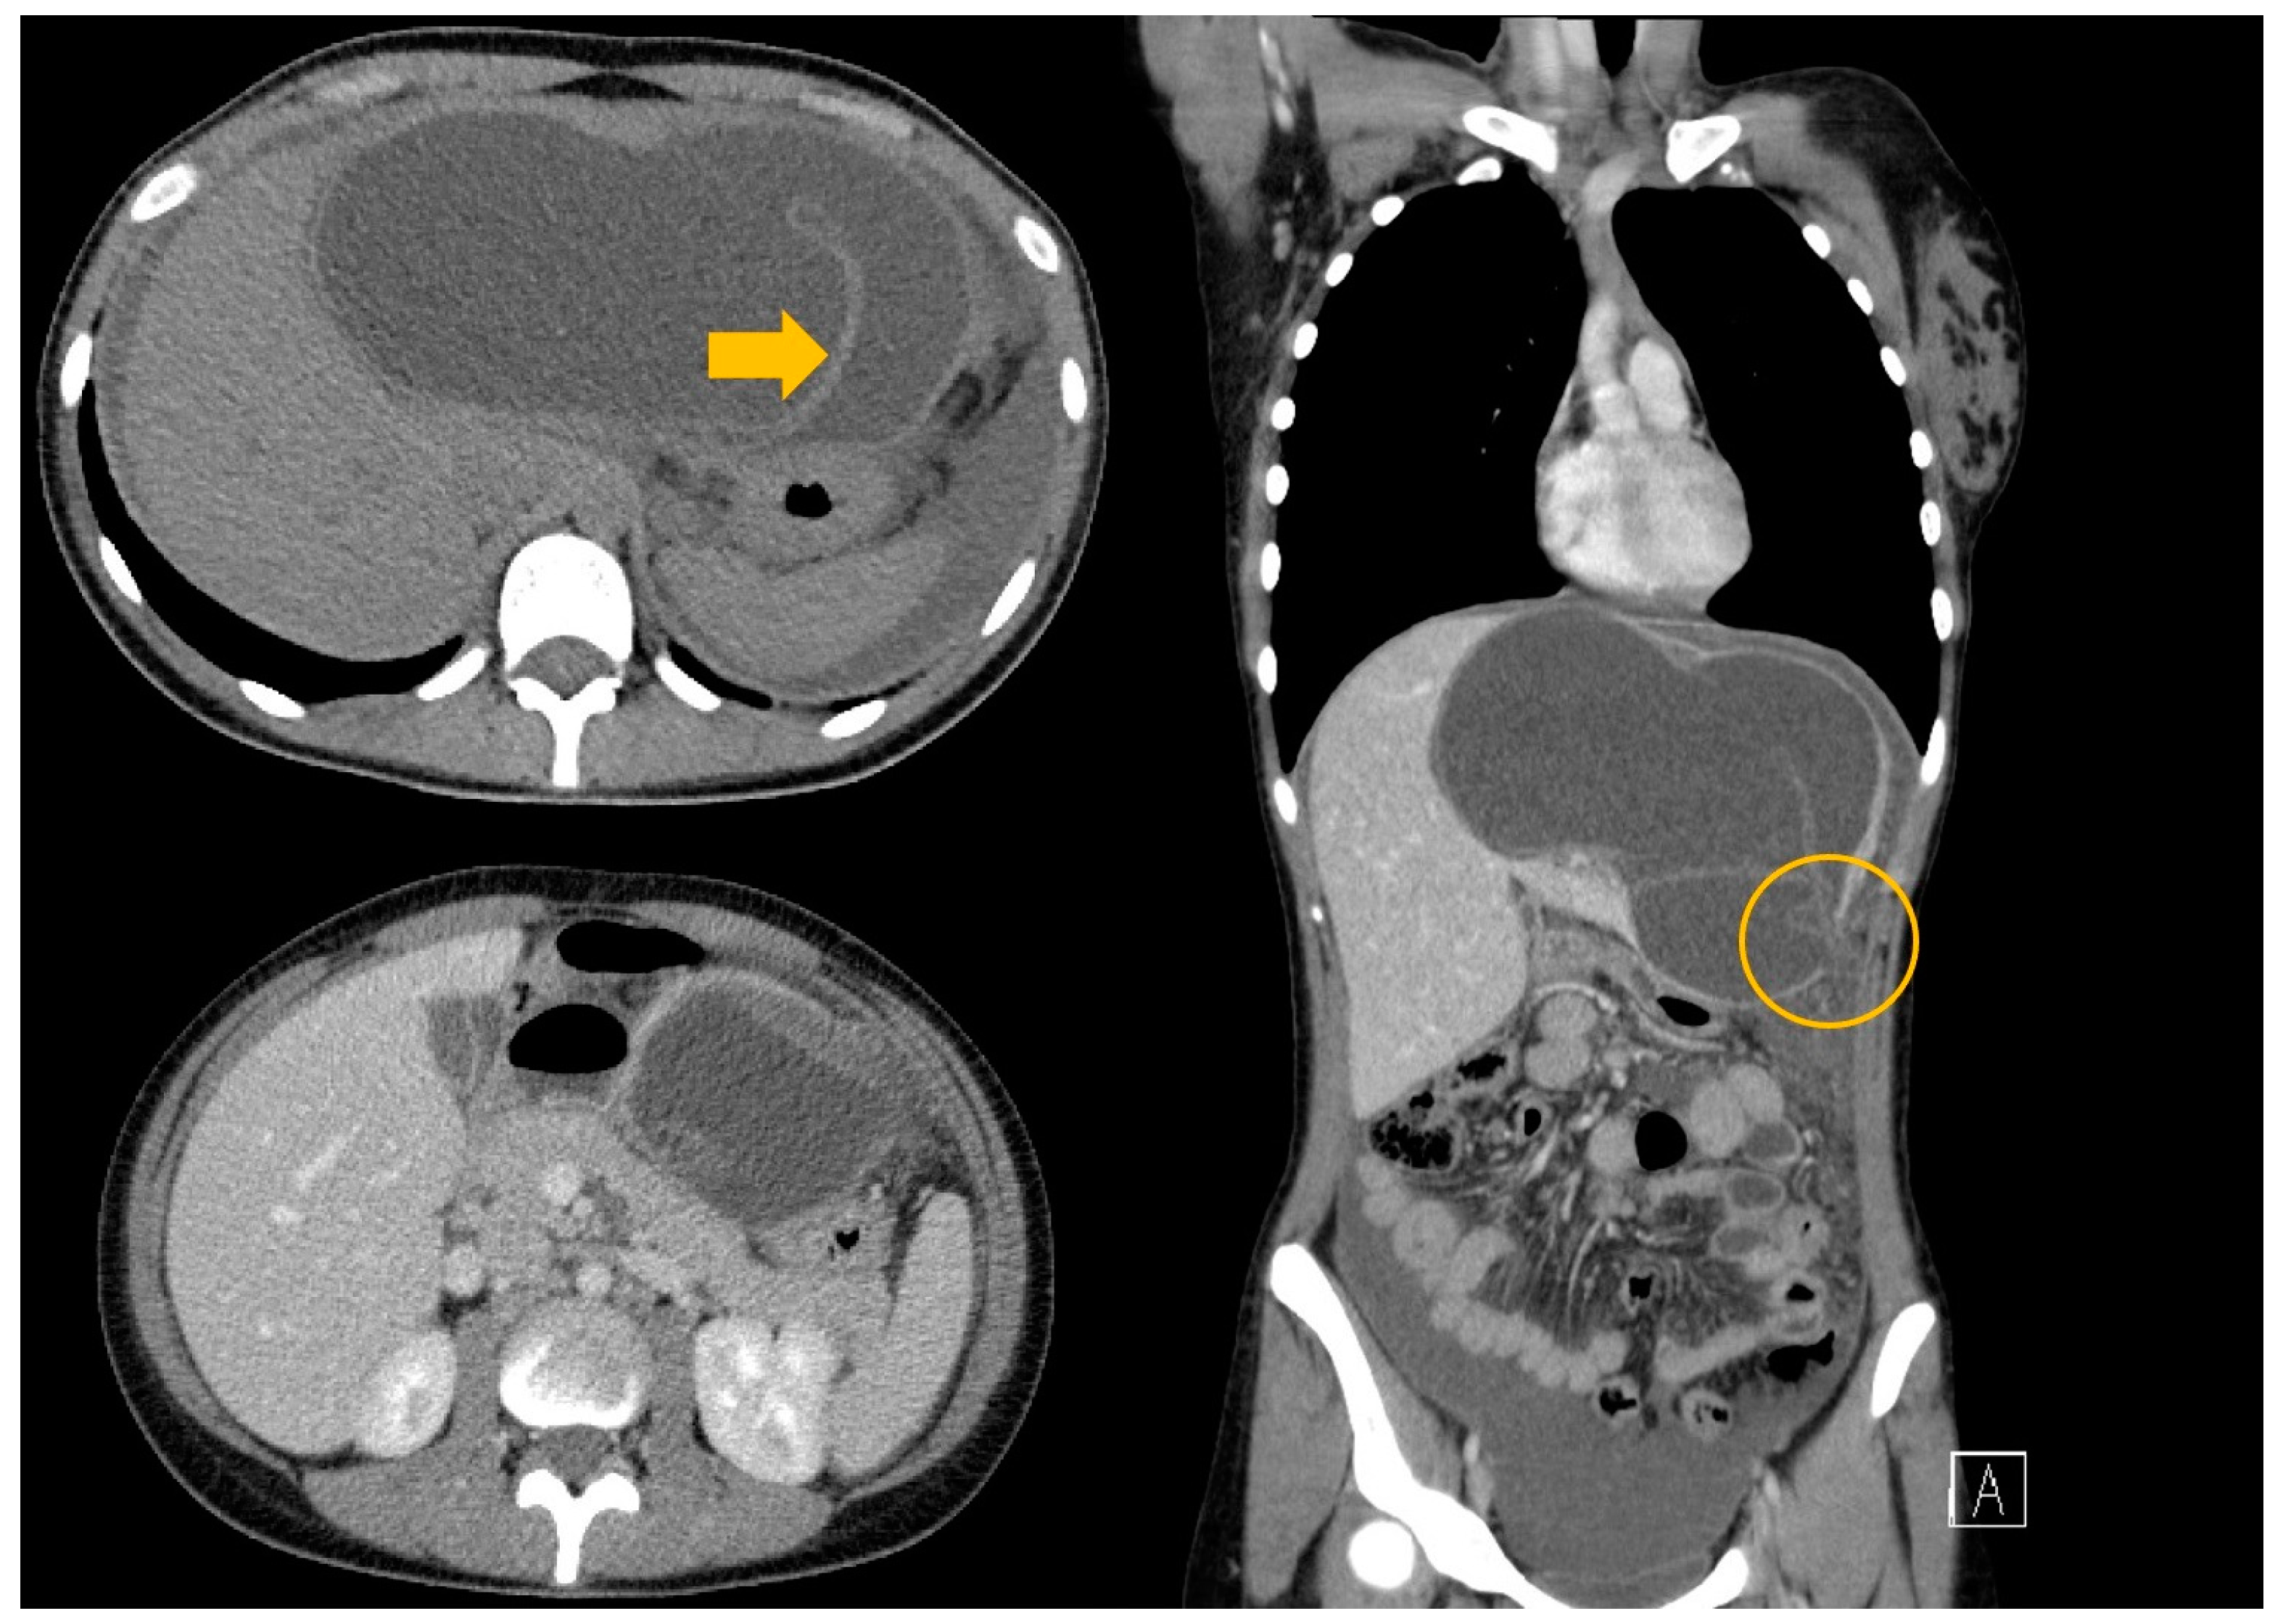

3.2. Case 2